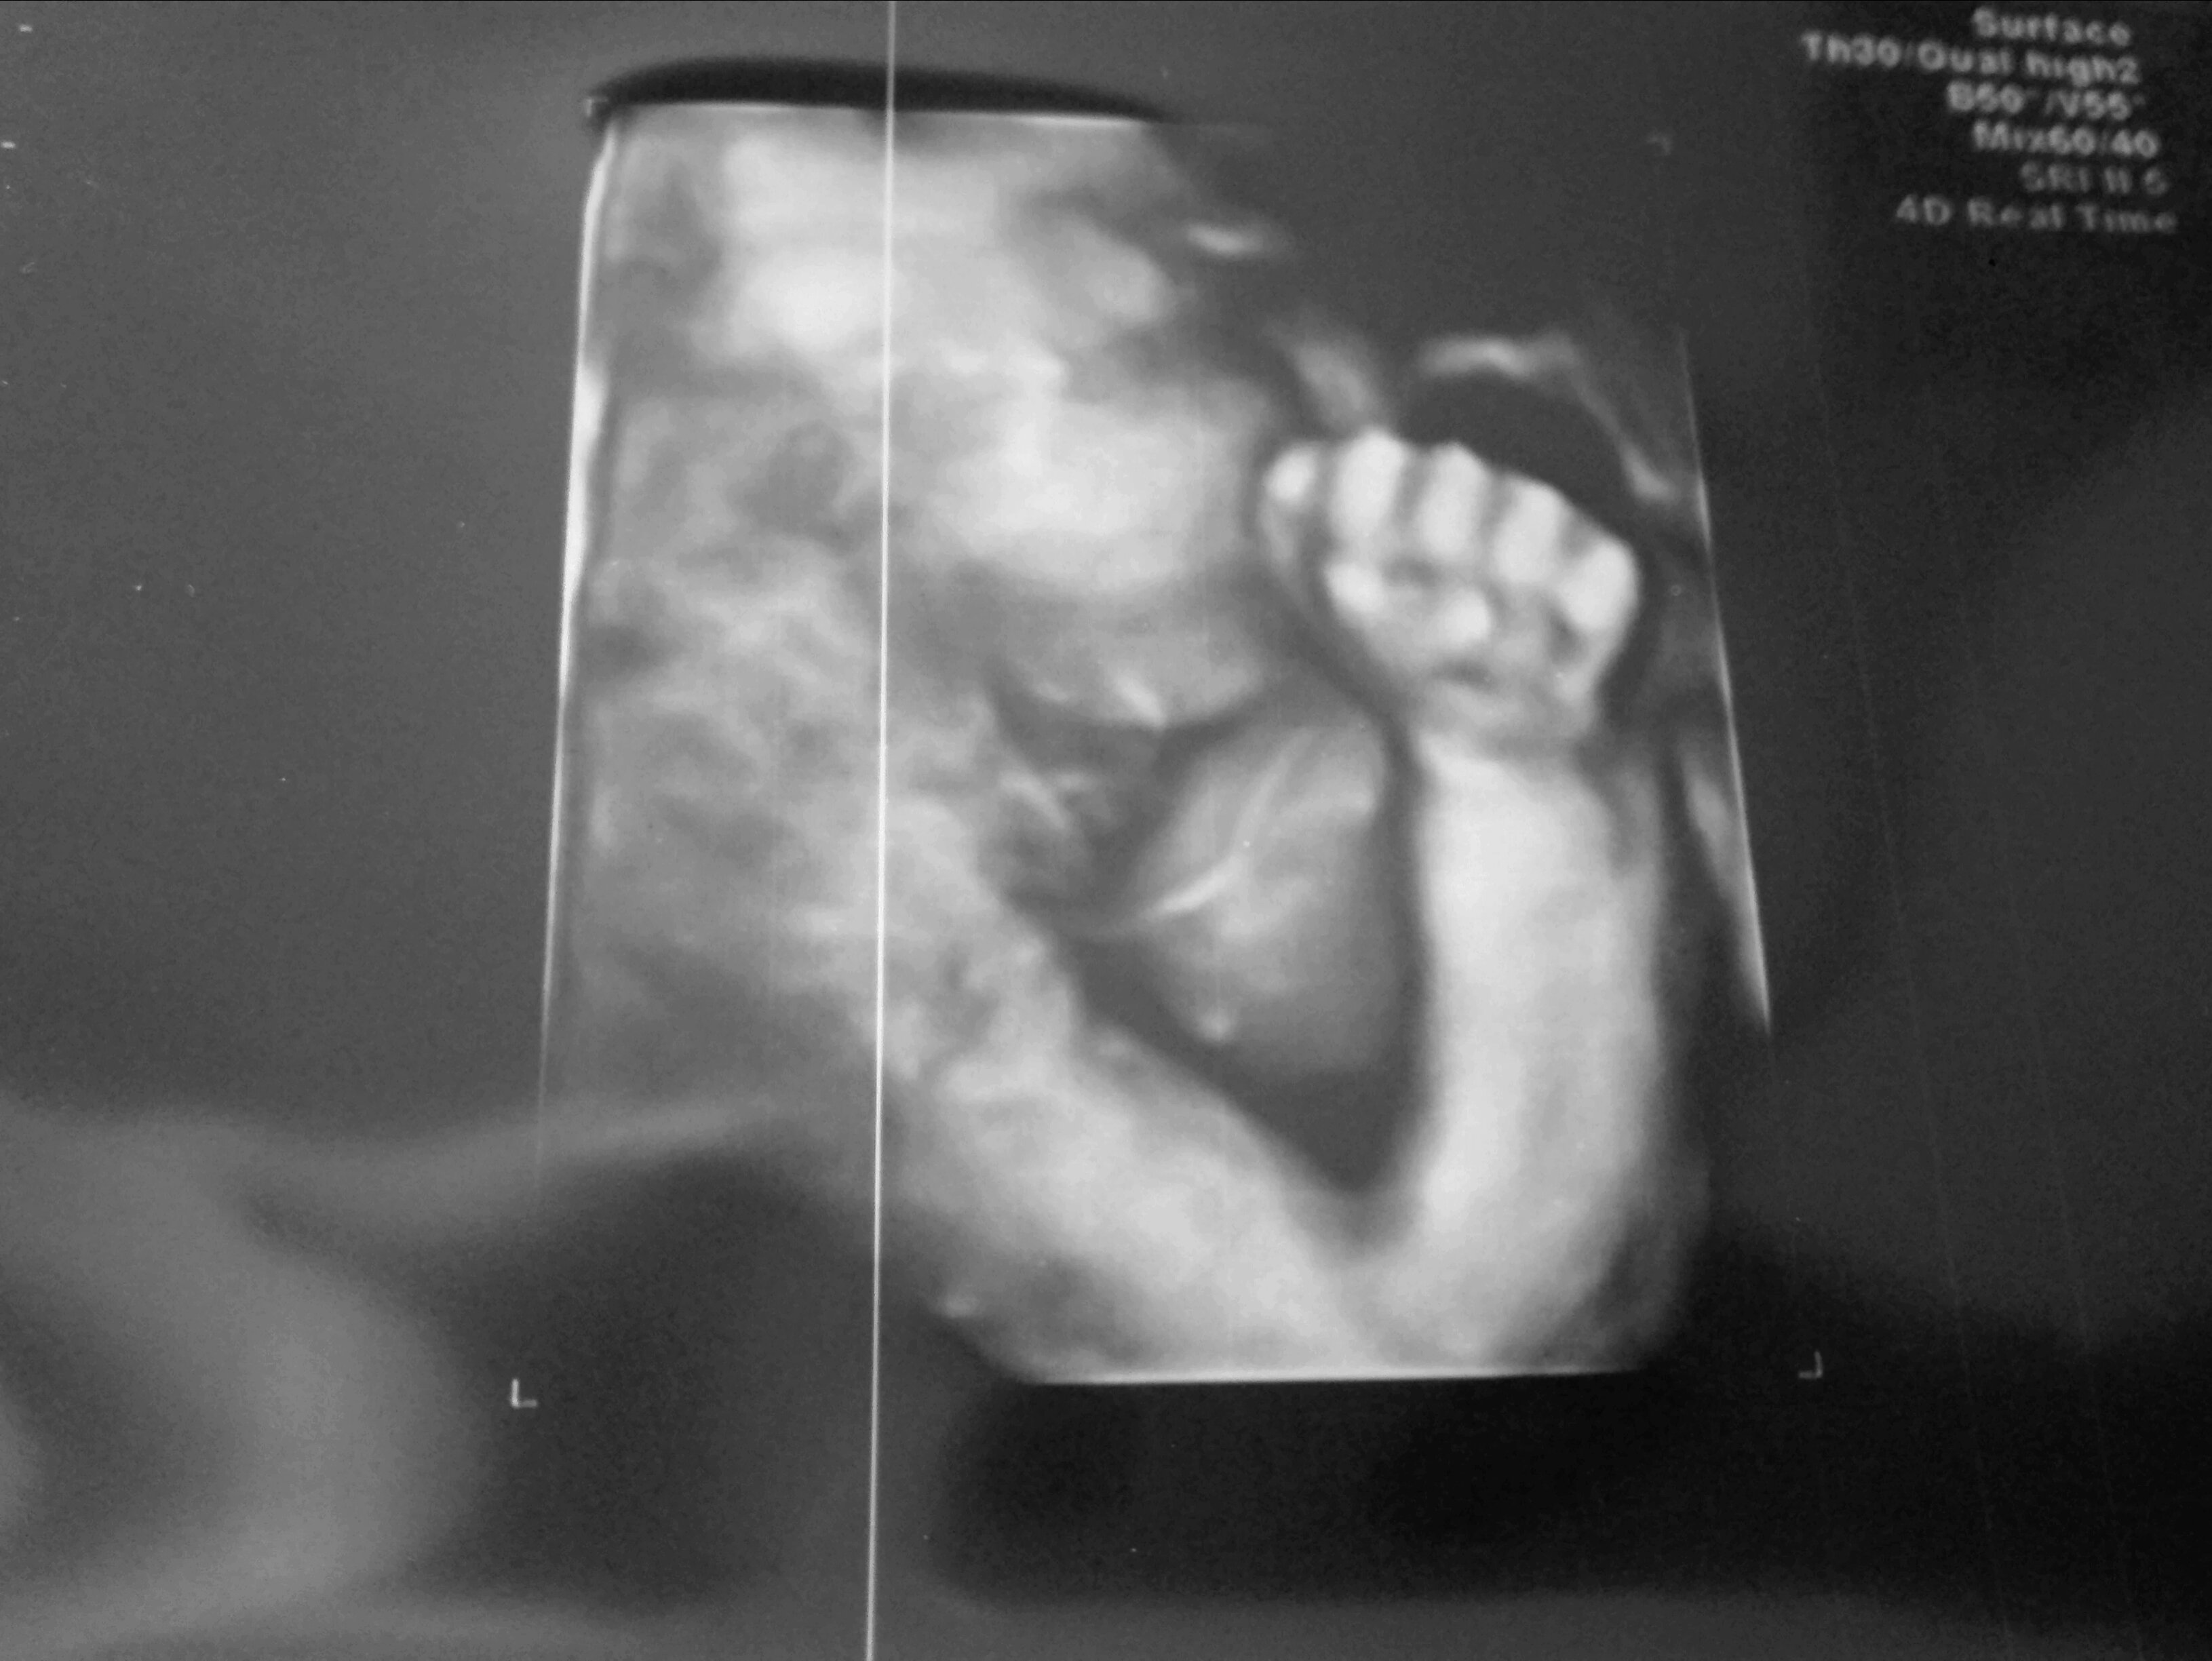

Mam już prawie 3 cmi jestem małym/łą wiercipiętą

Z brzucha mamy wychodzę 19 grudnia.

Świetny prezent pod choinkę, co nie ?

Zobacz załącznik 857539

A tu na zdjęciu złoczyńca wszystkich apetycznych posiłków przygotowywanych przez mamę...